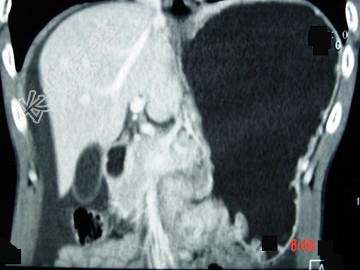

- 单项选择题男,65岁, 中上腹痛腹胀、消瘦、乏力、纳差,影像检查如图, 最可能的诊断是  (    )

- A、胃间质瘤

- B、萎缩性胃炎

- C、肥厚性胃炎

- D、胃窦癌

- E、胃淋巴瘤